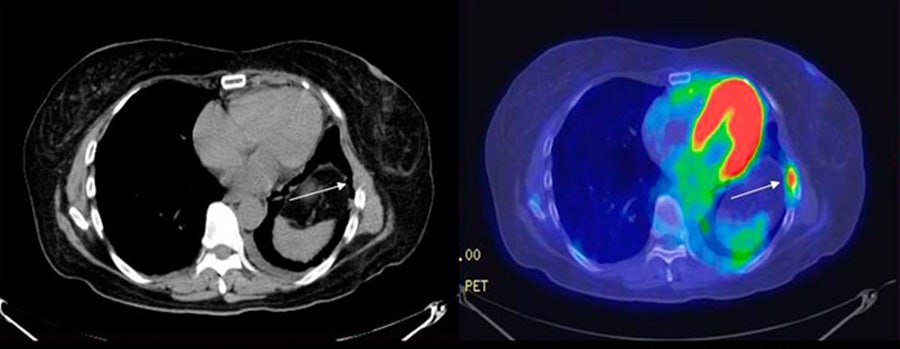

Процедура ПЭТ-КТ используется для выявления онкологических и неврологических заболеваний, а также патологий сердца

Процедура ПЭТ-КТ используется для выявления онкологических и неврологических заболеваний, а также патологий сердца. Она позволяет выявить злокачественные новообразования на ранней стадии, определить размеры и область её распространения.